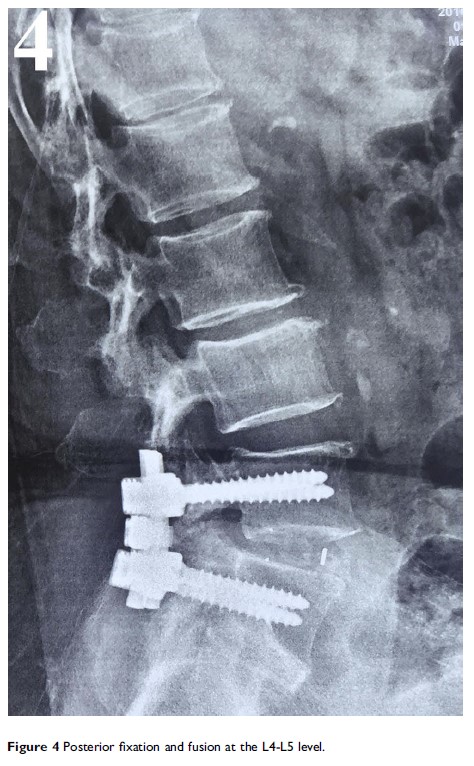

硬膜下型腰椎间盘突出:个案报道并相关文献回顾